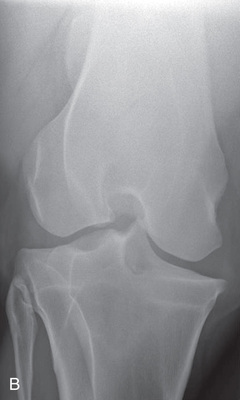

| Stifle | Lateromedial (LM) | Lateral (L) |

| Caudoproximal-craniodistal (CdPr-CrDi) | Caudocranial (CdCr) | |

| Lateral trochlear ridge and medial femoral condyle (stifle) | Caudoproximal 60-degree lateral–craniodistomedial oblique (Cd60L-CrMO) | CdLCrMO |

| Optional stifle | Cranioproximal-caudodistal (CrPr-CdDi) | Craniocaudal (CrCd) |

| Cranioproximal-craniodistal oblique(CrPr-CrDiO) | Skyline patella | |

| Lateromedial flexed (LM) | Flexed lateral (L) |

Radiography of the femorotibial joint (stifle) is difficult because of the thickness of the surrounding tissue and the sensitive nature of this region. Because of the depth of the muscle in the femoral region, the caudocranial projection demonstrates little above the joint space. Radiographs of this region should be attempted only if the patient is cooperative. Safety is paramount in radiography of the hind region of the horse. Sedation or a twitch may be used; general anesthesia is also to be considered.